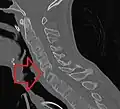

X-rays

The earliest changes demonstrable by plain X-ray shows erosions and sclerosis in sacroiliac joints. Progression of the erosions leads to widening of the joint space and bony sclerosis. X-ray spine can reveal squaring of vertebrae with bony spur formation called syndesmophyte. This causes the bamboo spine appearance. A drawback of X-ray diagnosis is the signs and symptoms of AS have usually been established as long as 7–10 years prior to X-ray-evident changes occurring on a plain film X-ray, which means a delay of as long as 10 years before adequate therapies can be introduced.[24]

X-ray showing bamboo spine in a person with ankylosing spondylitis

CT scan showing bamboo spine in ankylosing spondylitis